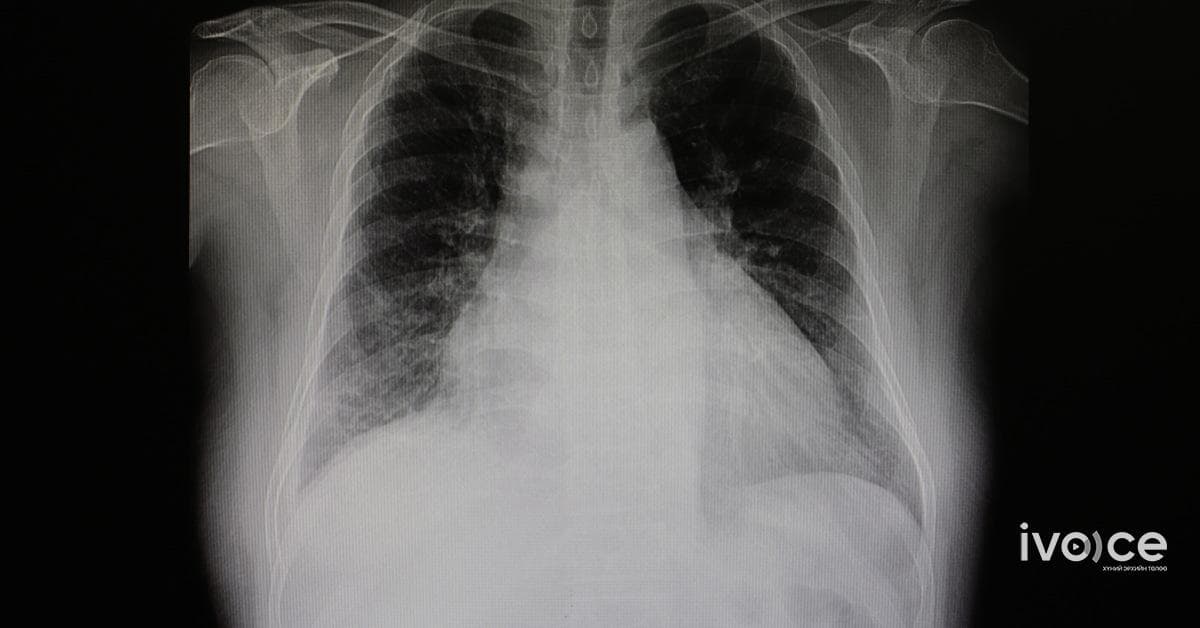

Хоёр жилийн турш өдөр бүр 2 энергийн ундаа уусан залуу зүрхний шигдээсээр нас барахад ойрхон байна